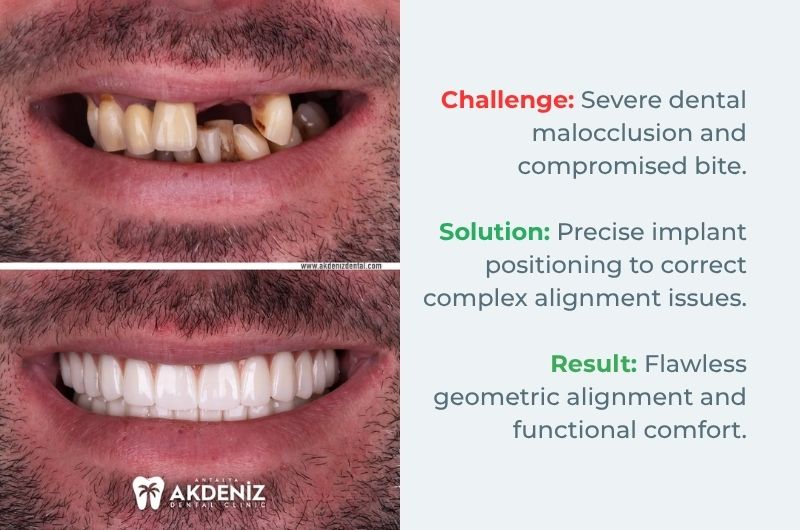

Geometric Alignment and Perfect Occlusion

Case Analysis 3:

In our third case, unlike the others, we encountered severe tooth crowding and malformation rather than significant bone loss. The 'before' photograph above shows an irregular structure where the teeth overlap, the occlusion is compromised, and cleaning has become impossible. By customising the All-on-4 technique for this case, our primary objective was to achieve flawless 'geometric alignment' and 'functional occlusion'.

Key Detail: The existing crooked teeth did not allow for the implants to be placed at ideal angles. Through digital planning, the implant positions were adjusted in such a way that the porcelain bridge placed over them completely resolved this complex geometry.

Result: As shown in the photograph below, the form, size and relationship of each tooth to the adjacent one were designed with mathematical precision. This not only restored aesthetics but also re-established the ideal occlusion (bite) necessary for the patient to chew correctly.